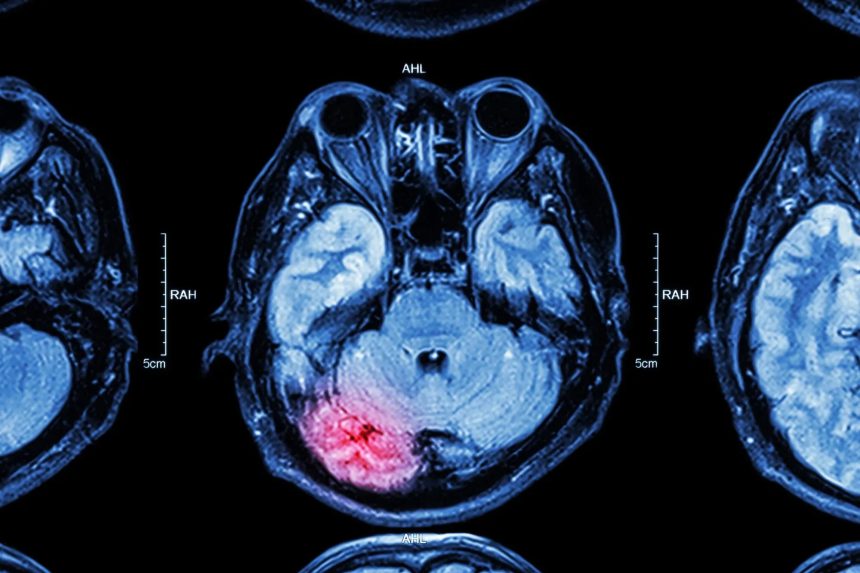

Výskumníci analyzovali mozgové tkanivo 15 zosnulých osôb vo veku od 33 do 100 rokov. U ôsmich z nich objavili mikroplasty v čuchovej cibuľke, časti mozgu zodpovednej za spracovanie vôní. Tento objav naznačuje, že mikroplasty môžu prenikať do mozgu cez nosovú dutinu, konkrétne cez čuchové nervy, ktoré vedú priamo do mozgu.

Okrem toho odborníci nevylučujú, že mikroplasty sa môžu do mozgu dostať aj cez krvný obeh. Po konzumácii potravín a vody obsahujúcich tieto čiastočky sa mikroplasty môžu dostať do krvi a potenciálne prekonať krvno-mozgovú bariéru, ktorá bežne chráni mozog pred škodlivými látkami.

Štúdia zverejnená v máji 2024 naznačuje, že mozog môže obsahovať až 20-krát vyššiu koncentráciu mikroplastov v porovnaní s inými orgánmi. Odhaduje sa, že mikroplasty môžu tvoriť až 0,5 % celkovej hmotnosti mozgu. Presné miesta, kde sa tieto čiastočky hromadia, však zatiaľ nie sú úplne známe.